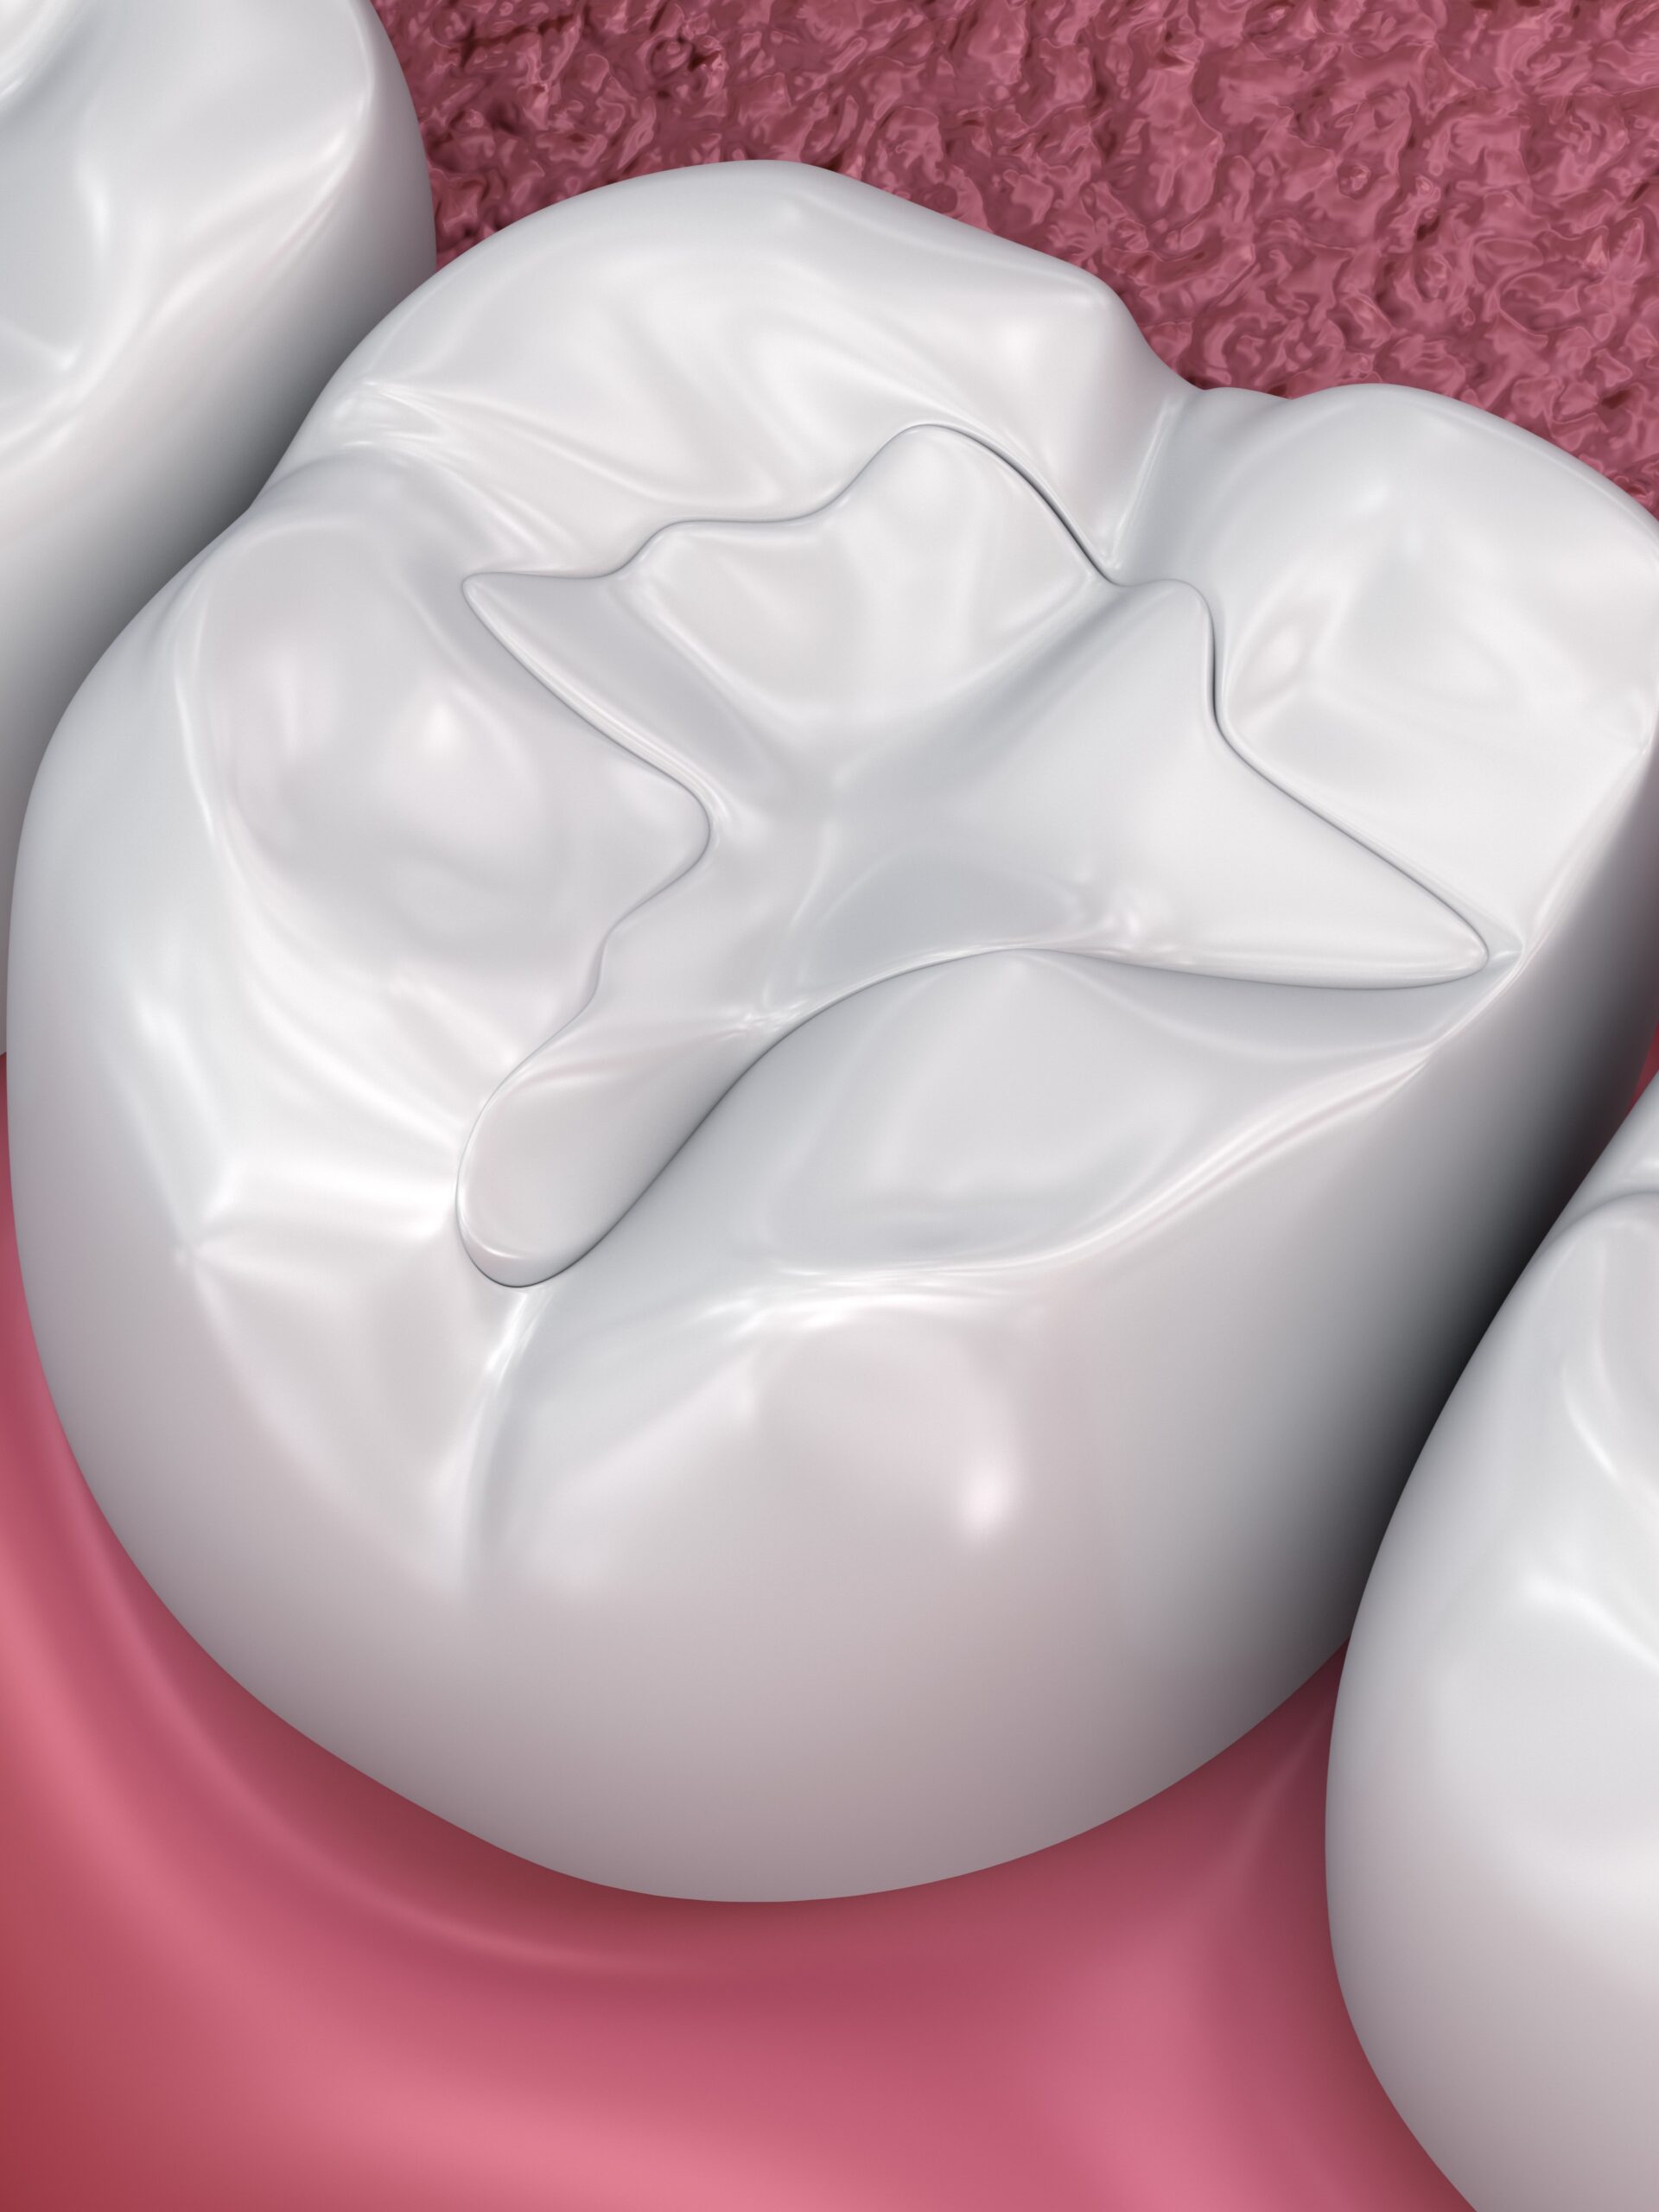

Moderne alternative Füllungsmaterialien wie Kunststoff (Komposit) oder Keramik stellen eine sichere und ästhetisch ansprechende Lösung für Zahnreparaturen dar. Sie sind stabiler und haben ein viel kleineres Risiko für Zahnfrakturen.

Neue biokompatible Kompositfüllung in der zum Zahn passenden Farbe.